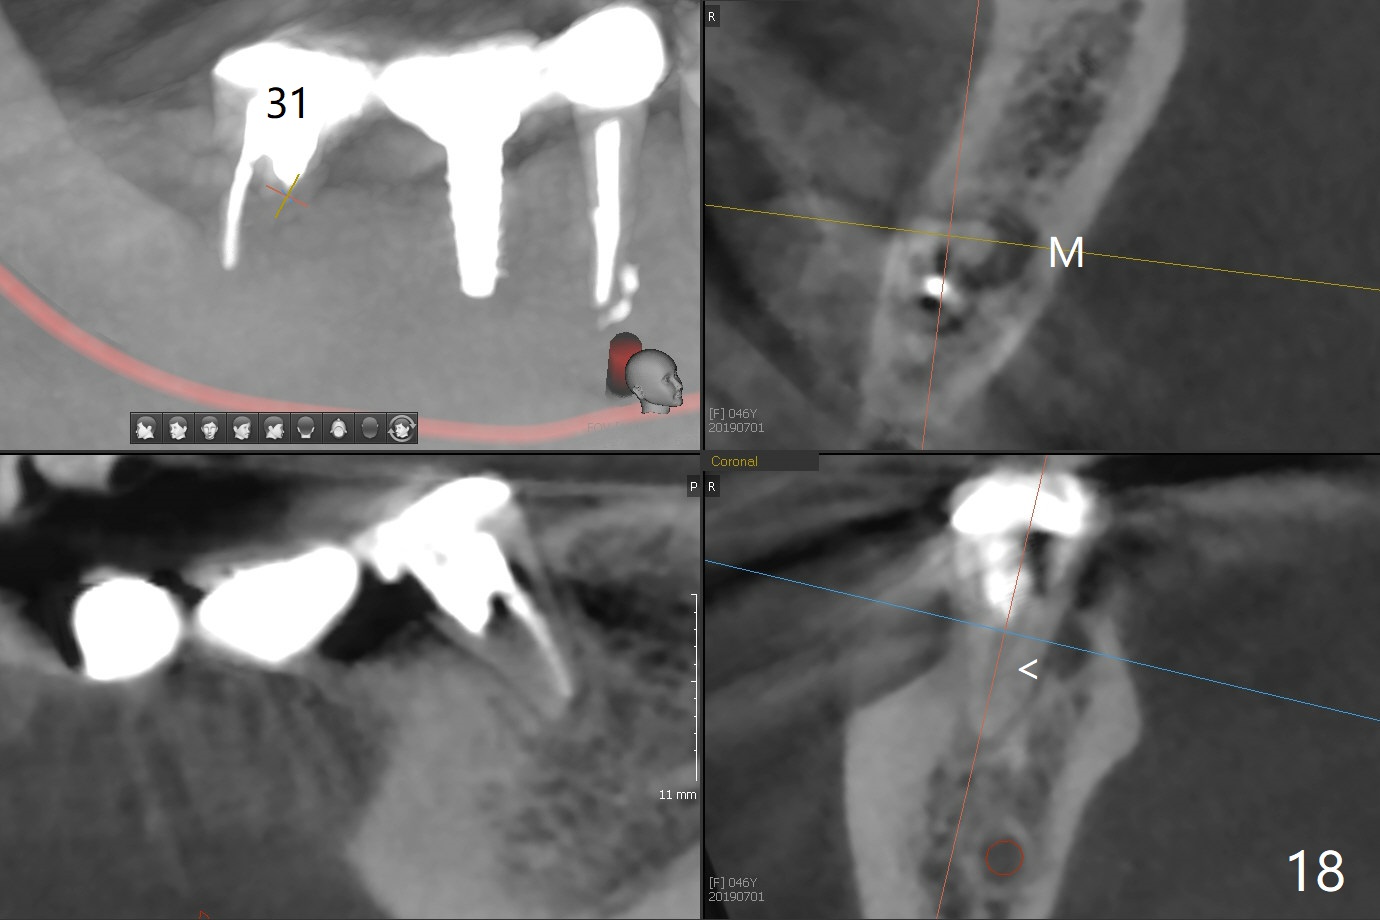

CBCT was taken (Fig.1,2 (P: pontic; S; submandibular fossa)) several months prior to #29 and 31 RCT and #31 porcelain chip (Fig.3). When the bridge is sectioned, the pointed ridge at #30 (Fig.1) is confirmed (Fig.4,5). After flattening the ridge until 6 mm buccolingually (Fig.6 arrowheads), osteotomy is initiated with 1.6 mm drill at 9 mm; there is 2.5 mm clearance from the superior border of the Inferior Alveolar Canal (red dashed line). A 4.5x9(1) mm Magicore is placed with 35 Ncm (insertion torque) after 4.3 mm Magic Drill; a 4.5 mm healing abutment (Fig.7 H). An error occurs because of using 1 mm cuff of the Magicore. Ideally 3 or 4 mm cuff should have been used because of reduction of the ridge by ~ 3 mm (Fig.2). The result of the error is failure of placing the implant at the desirable depth (<9 mm). The coronal threads are exposed and have to be covered by bone graft (autogenous bone and allograft (.5-1.5 mm) (Fig.8 *), followed by collagen dressing. Extra suturing is done to securely close the wound (Fig.9), followed by periodontal dressing (data not shown).

The wound is healing 8 days postop (Fig.10). Because of the short cuff (subgingival margin), screw retention type of restoration will be used, in contrast to cement type of the 2nd case. In fact, FC one is used.

Splinted provisional is fabricated #30 and 31 one month postop. The patient returns for final restoration (single units) nearly 4 months postop (Fig.11). Since the margin is subgingival, a screw type crown is fabricated for #30 (Fig.12). The buccal gingiva looks convex after healing cap removal (Fig.13, as compared to Fig.4 (concave)). PA is taken immediately post tightening and cementation (Fig.14, 5 months postop). It appears that new bone has grown between the most coronal threads (arrows). The bone density immediately around the implant appears to increase 1.5 years post cementation (Fig.15,16). She returns because of failure of 18-20 bridge (implants will be placed at 18/19). The implant at #30 is in fact not placed deep enough; the coronal threads seem to be exposed, although there is no periimplantitis (Fig.17 CT). The tooth #31 is symptomatic; the mesial canal is missing (Fig.18 M, <). The gingiva around the crowns at #30 and 31 remains healthy 2 years 4 months post cementation (Fig.19). Metal exposure of the crown at #31 is intentional. Occlusal reduction is done to alleviate periapical re-infection (Fig.18).